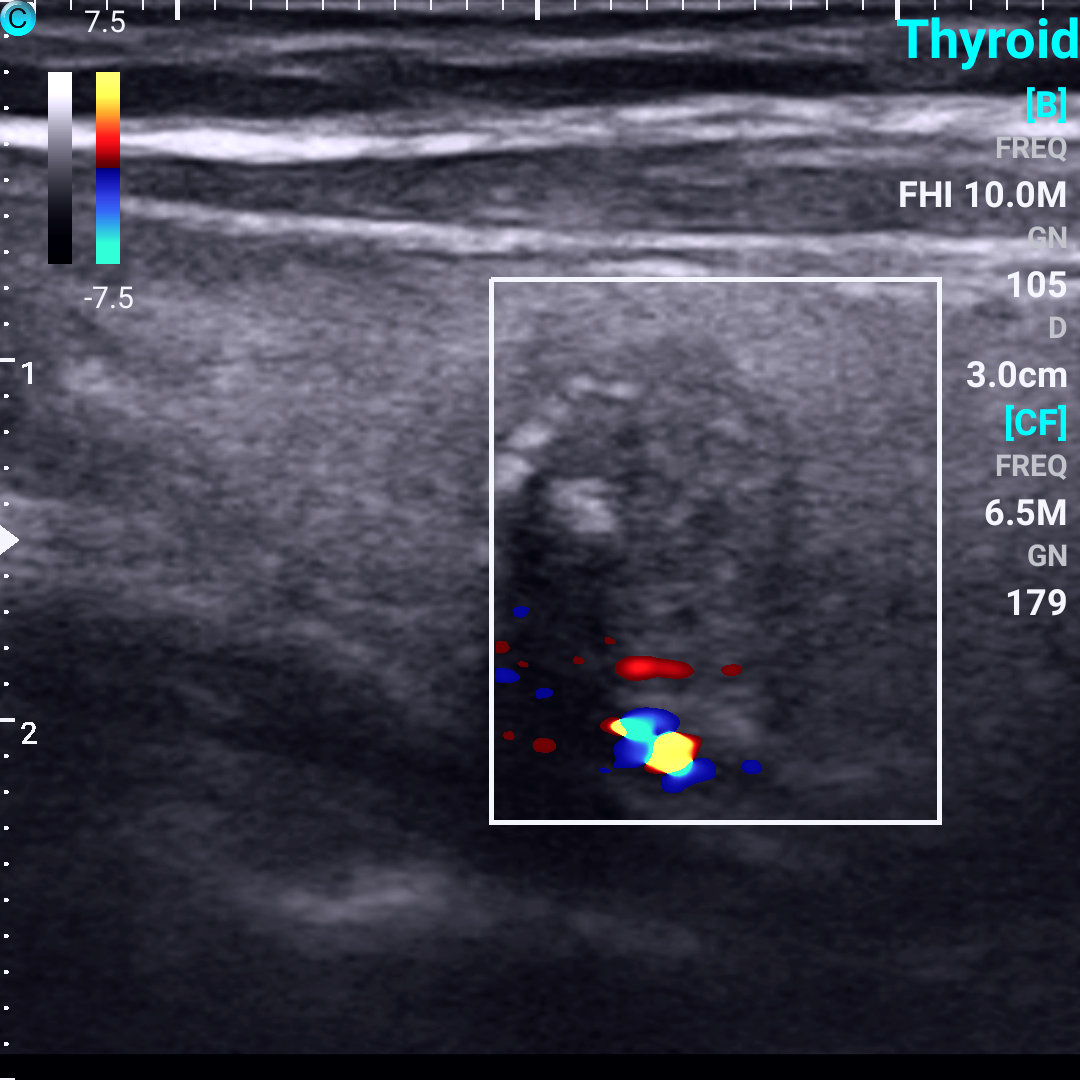

05、看血流

1. 结节内部无血供,结节周边为环状血流信号,提示结节为良性

2. 结节内部血流信号分布紊乱,多由结节周边向内部穿入,提示结节为恶性。

甲状腺结节中血流图像